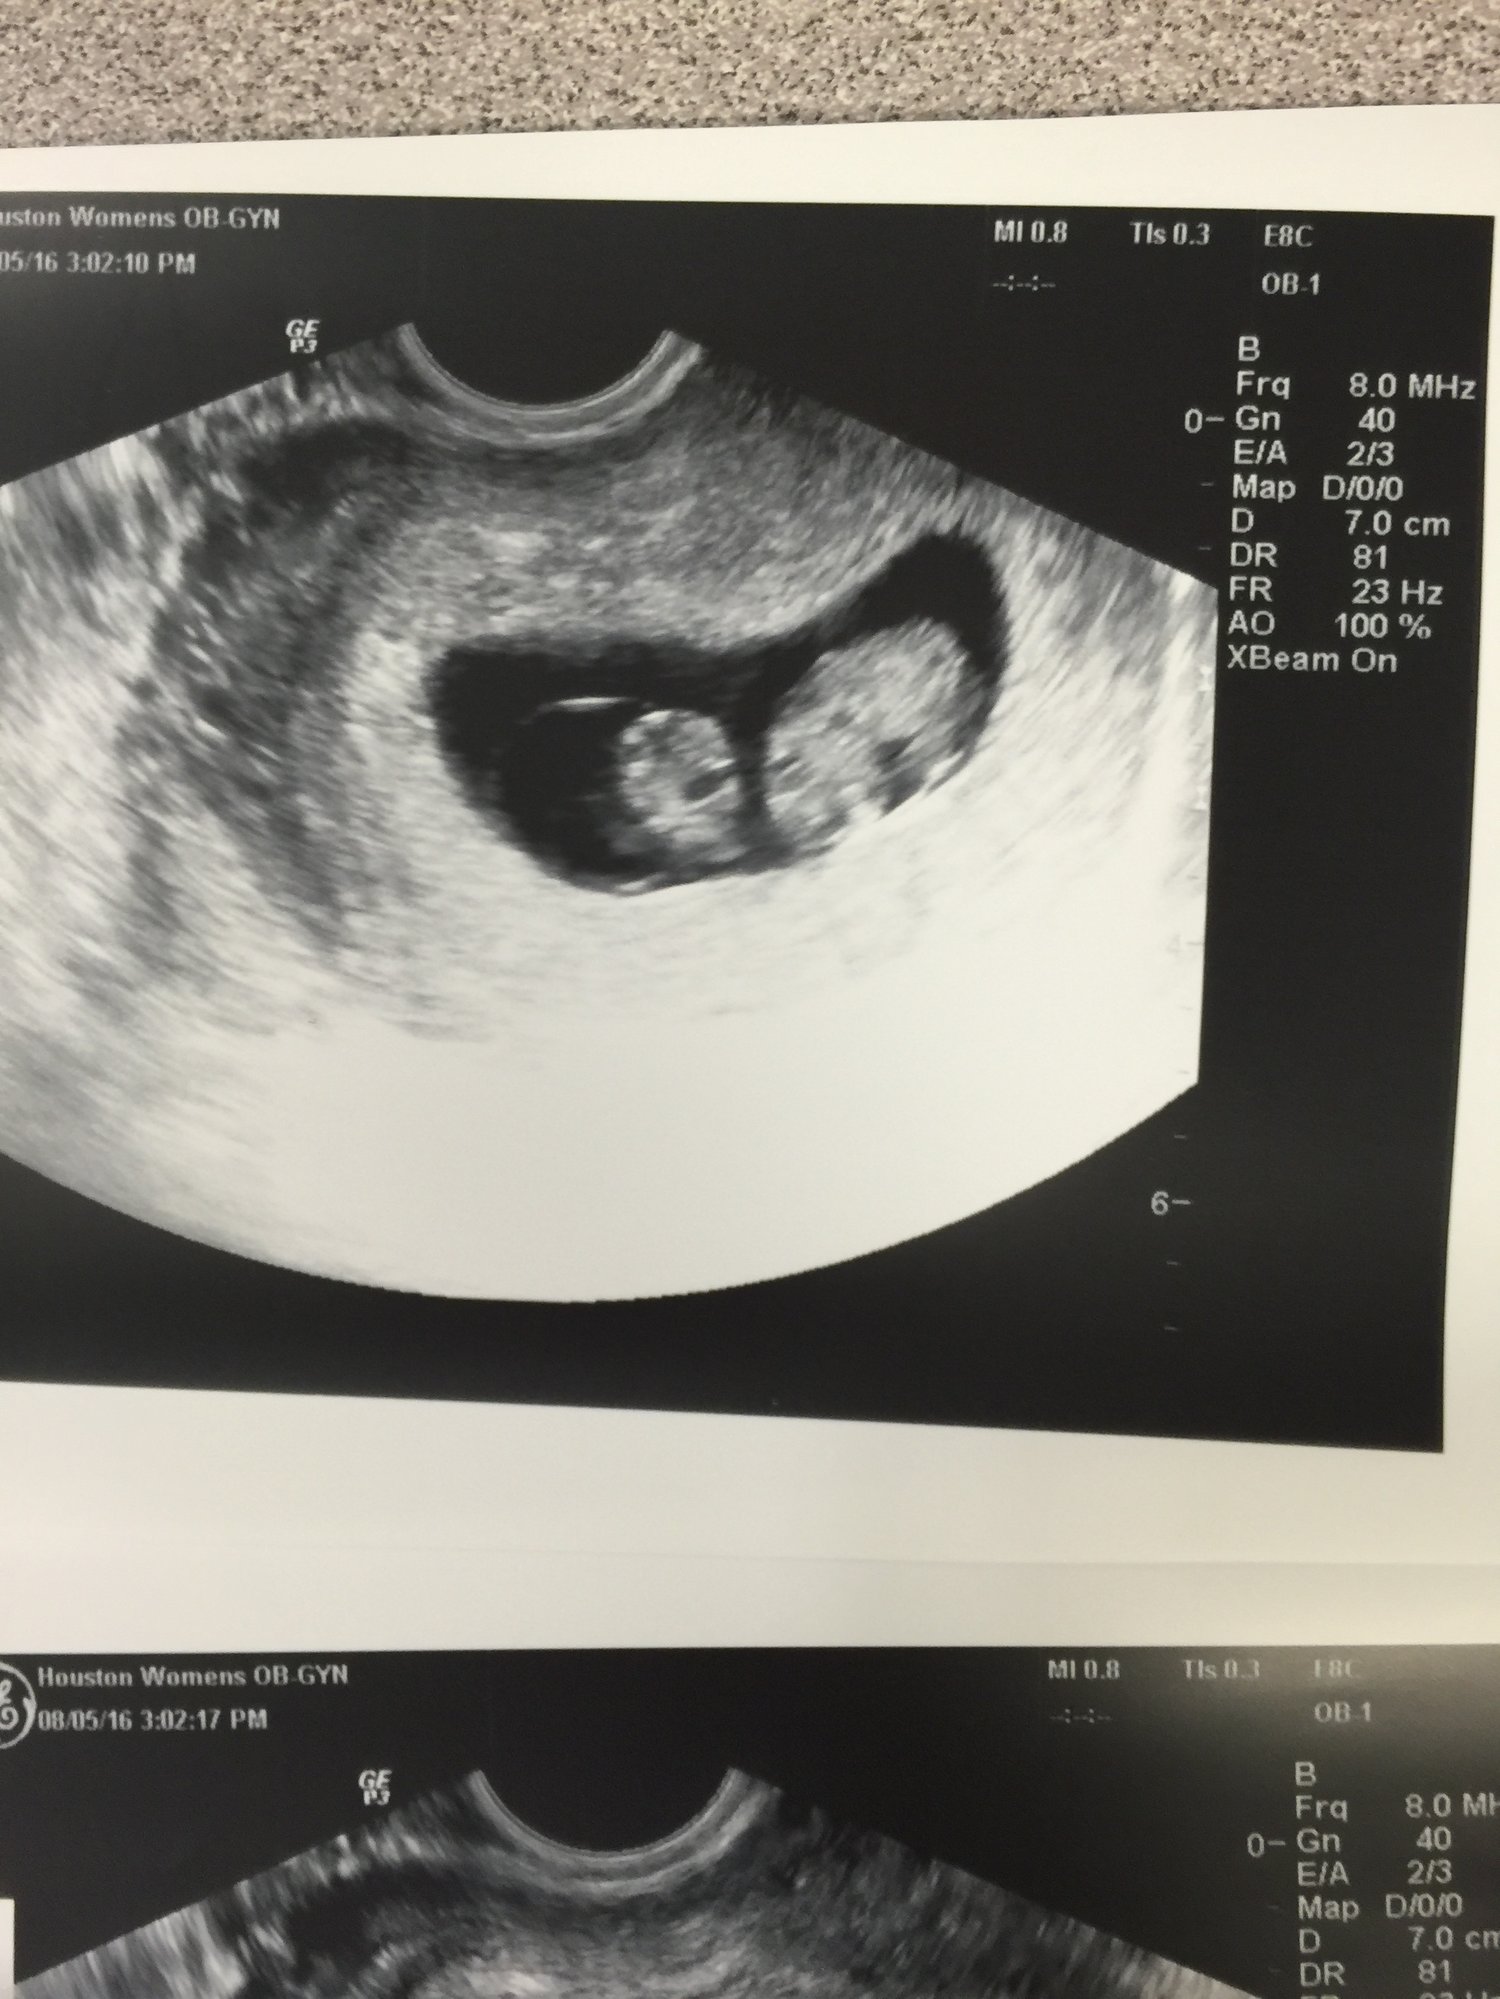

update: so my high risk obgyn (which is going to be the consultant to my regular obgyn) performed an ultrasound last Friday with a better machine. babies are doing great. however she thinks they are smaller than LMP by 5-7 days, ( so a little over 7 weeks instead of a little over 8 weeks) due date still in march though. maybe I ovulated later? but they are good sizes, good heart beats. and she thinks they are mono-di. which is good. but now I have to worry about other stuff like twin on twin transfusion.

Had aother ultrasound today! Babies are measuring 9 weeks and growing good they really think they are mono di now. And one of them is sideways. So 3 pix. One is twin a and b seperate and the one with them together but not in the same position. U only see the side head viewish. Strong heart beats 179 and 181 *grow grow babies grow grow* doing the genetics blood test next week which, since they are identical, should tell us the gender! Yay

i was all worried going in, and got so emo when I heard their heart beats as always. The little nubs for hands and legs are there. One of them was wiggly a little too!